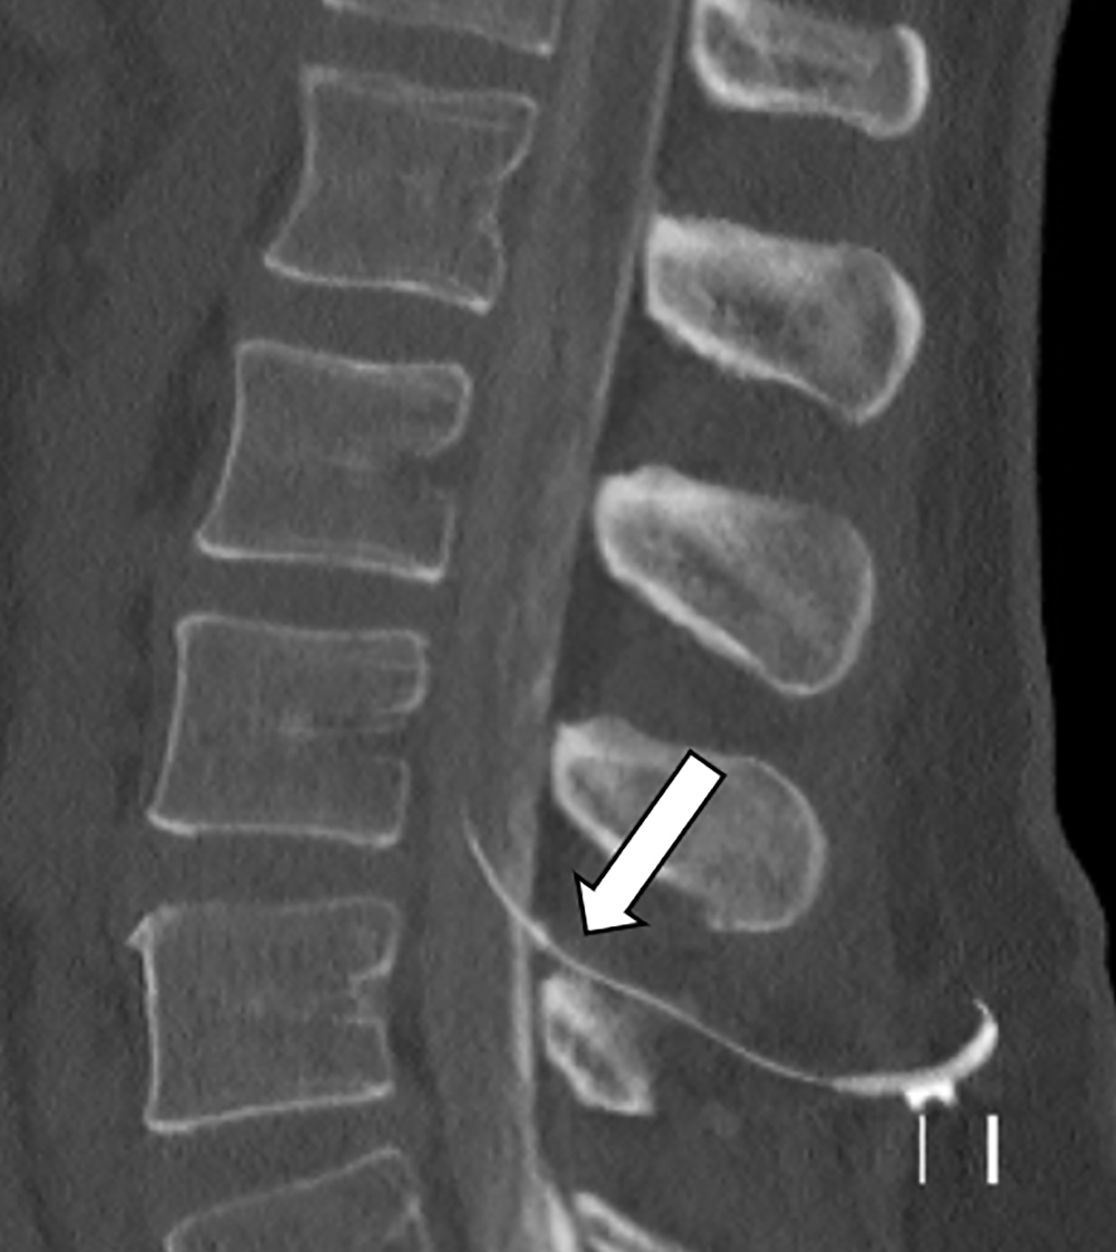

Bei Patienten mit schwerer Spastik oder chronischen Schmerzen, die nicht ausreichend auf herkömmliche medikamentöse Therapien ansprechen, kann die Implantation einer Schmerzpumpe eine effektive Lösung darstellen. Diese Pumpe ermöglicht die direkte Abgabe von Schmerzmitteln oder muskelentspannenden Medikamenten in den Nervenwasserraum (intrathekal), was eine deutlich gezieltere Wirkung mit geringeren Nebenwirkungen ermöglicht als bei in Tablettenform eingenommenen Medikamenten.

Das Pumpensystem besteht aus einem kleinen Schlauch, welcher in den Nervenwasserraum eingebracht wird und mit der Pumpe verbunden ist. Die Pumpe wird meist am Bauch unter der Haut implantiert und ermöglicht, dass die Dosierung der Medikamente exakt an die Bedürfnisse angepasst werden kann. Es ist eine regelmäßige Wiederbefüllung der Pumpe mit den Medikamenten notwendig, was ähnlich wie bei einer Blutabnahme von außen erfolgt.

In unserer Klinik bieten wir Ihnen eine ausführliche Beratung, die Implantation sowie die kontinuierliche Nachsorge dieser Therapie, um Ihre Beschwerden bestmöglich zu lindern und Ihre Lebensqualität zu steigern.

Im Nervenwasserraum (Liquor) einliegender Schlauch zur intrathekalen Therapie (Pfeil)